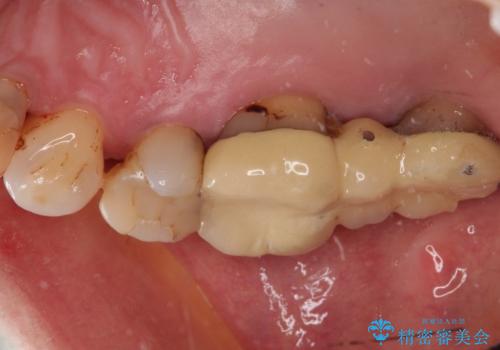

歯周病の進行した歯の抜歯。オールセラミッククラウン

- 以前に他院にて治療した歯が痛いことを主訴に来院されました。

最後方臼歯は根尖部まで歯周病が進行しており、抜歯を行なったのち、残存歯は歯周外科を行なったのちオールセラミッククラウンにて修復治療を行なっています。